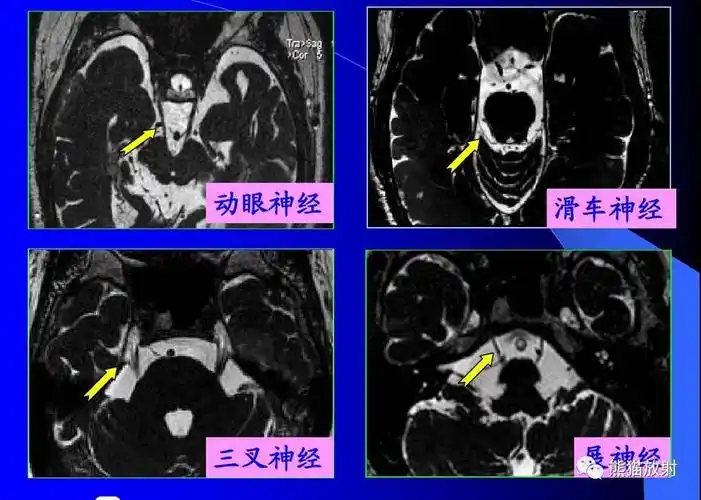

面神经解剖与常见疾病

面神经解剖及相关病变